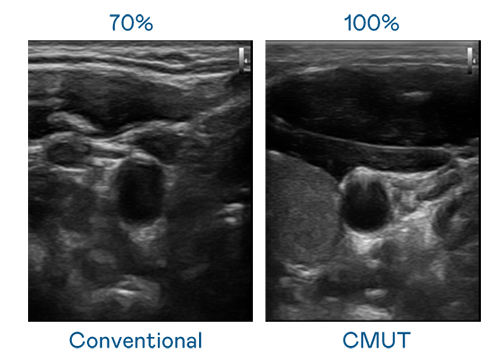

CMUT 技术是一种用电容式微机电元件来产生超音波讯号的技术。与传统 PZT 压电式技术相比,CMUT 频宽增加 30%,更宽频的超音波讯号让影像解析度大幅提升,是实现高影像品质医疗超音波扫描、促进精准医疗发展的关键技术。

超音波影像的解析度高低,首先取决于探头能发出的讯号频宽。尊龙凯龙时人生就是博网址 CMUT 可提供高清晰的超音波讯号,提供高频宽、高灵敏度、影像纹理细节更高的超音波影像,协助医护人员缩短影像判读时间及利用精准的医疗影像进行诊断。